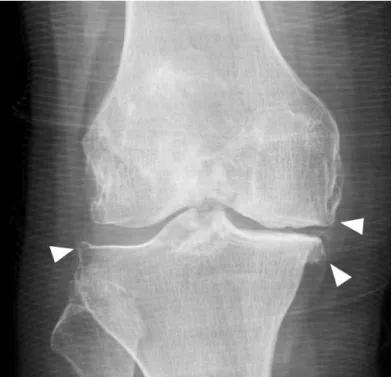

有的长时间下蹲后不能站立,有的走平路时也出现疼痛,去医院一拍片,膝关节长骨刺了,这究竟是怎么回事呢?

骨刺的称呼有很多,例如“骨赘”、“骨质增生”等。

骨刺的形成是膝关节衰老到一定阶段的必然结果,也是膝关节骨性关节炎的特征性表现。

此外,骨性关节炎还会引起关节软骨破坏,关节囊增厚等变化。“骨刺”这个名字听起来似乎很可怕,但是,实际上呢,这是错的,因为:

久而久之,就形成了X片上可以看到的骨刺。